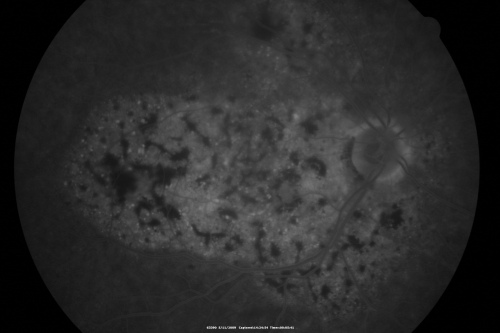

Bilateral Diffuse Uveal Melanocytic Proliferation - BDUMP - Paraneoplastic Syndrome

80-year-old man vision loss for one year.  He died about one year after these photos from Metastatic Poorly Differentiated Large Cell Carcinoma of unknown primary.  He was a smoker.